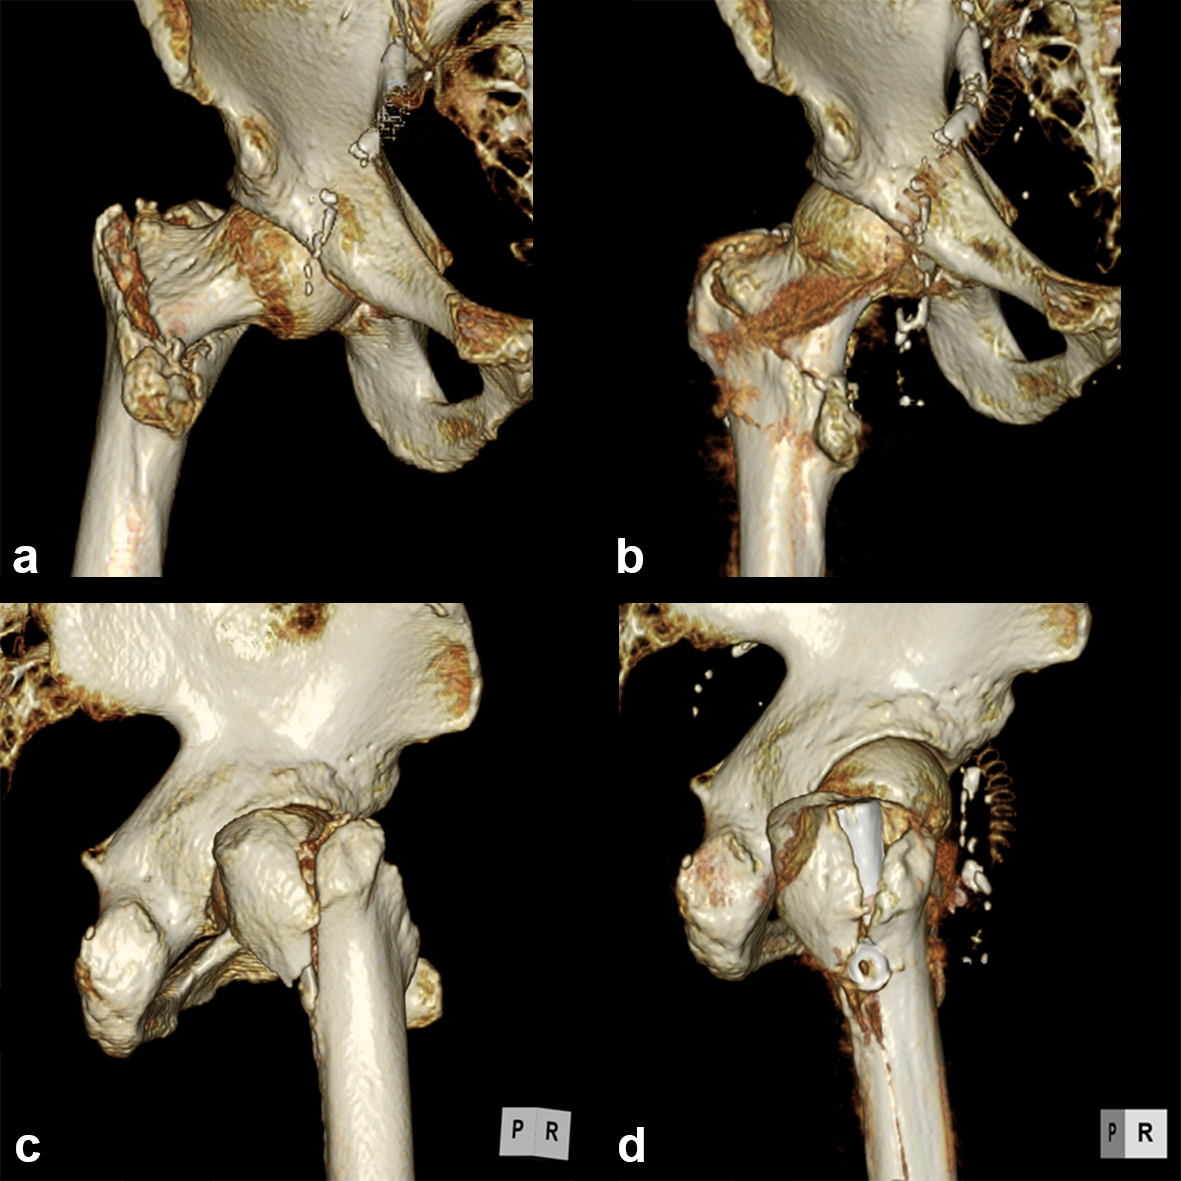

It is widely reported in the literature in Japan that there are many missed unstable femoral trochanteric fracture cases diagnosed only by x-ray, yet CT scans can clearly reveal the unstable fracture pattern.

A 77-year-old man suffered a right femoral trochanteric fracture (Figs 5-8). This case can be diagnosed as AO31-A1. However, the CT shows the detachment of the lesser trochanter (AO31-A2). Precise information of dangerous fracture patterns in advance might simplify the imaging of intraoperative reduction maneuvers and the use of the implants.

In this case, the fracture lines are located in the area of the intended nail insertion point. The 3-D reconstruction images distinctly show that the hollow reamer prevented the fracture fragments from being pushed apart when introducing the hollow reamer close to the fracture line.